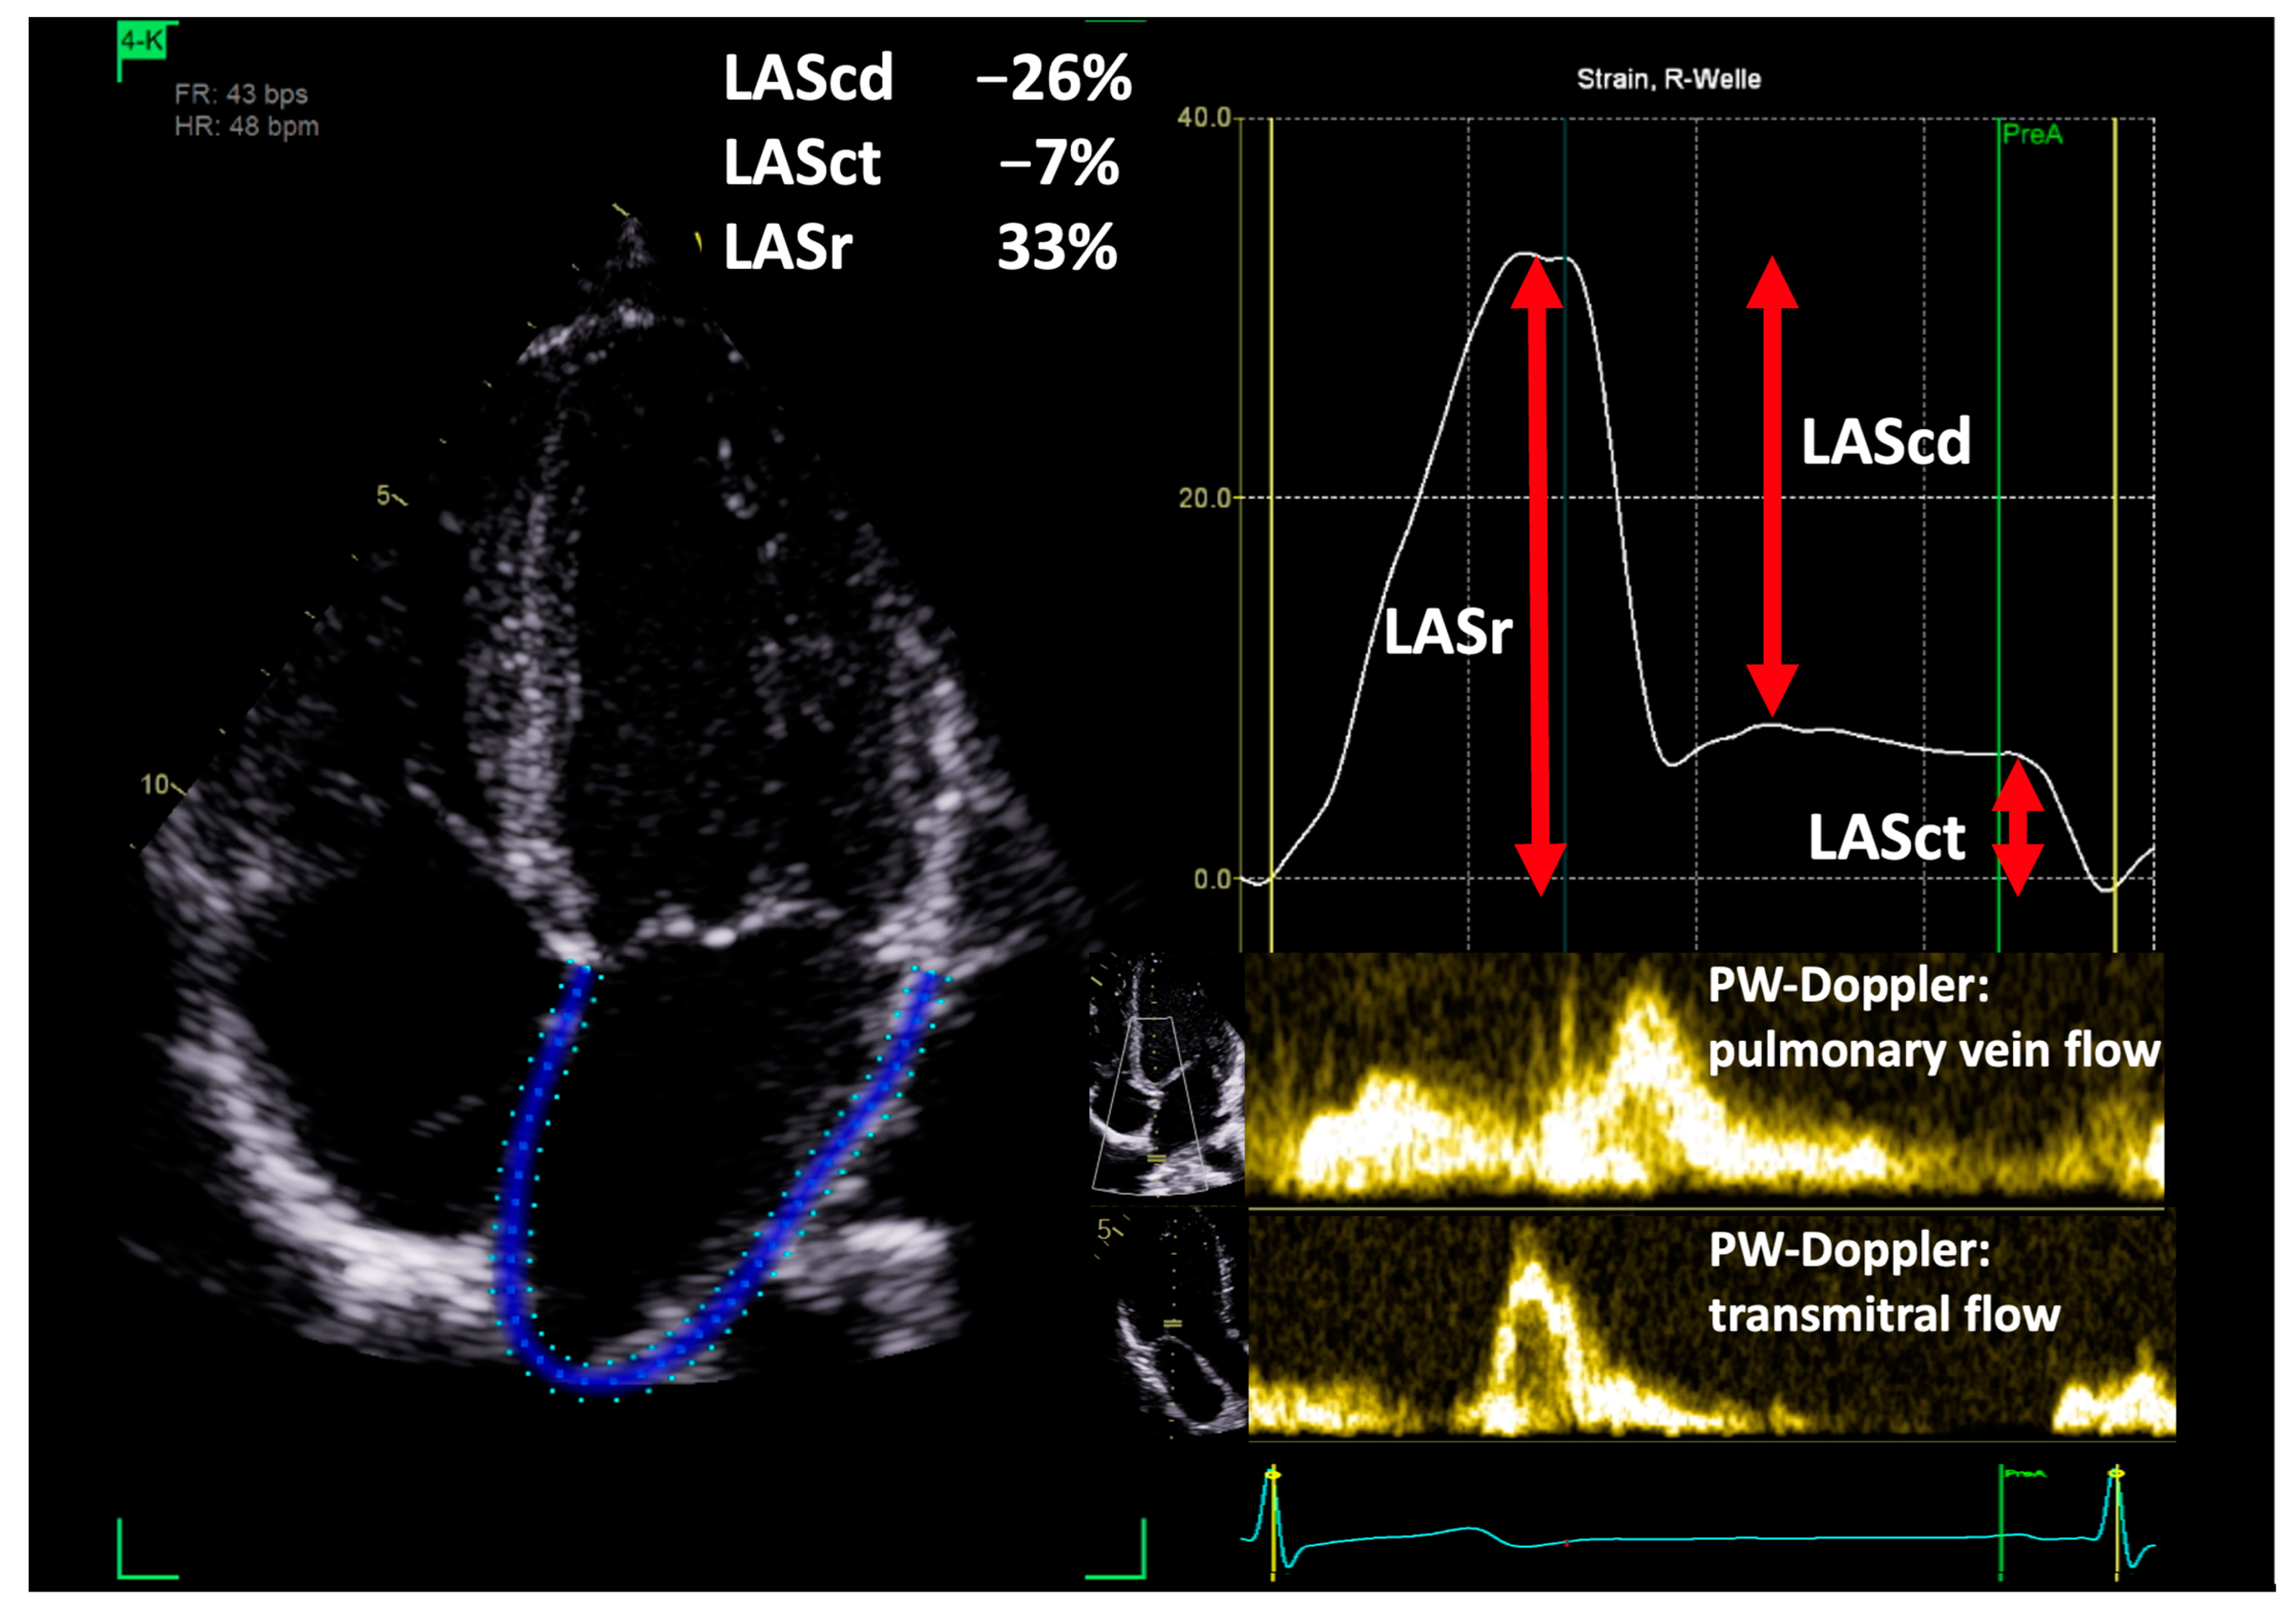

2.2. Parameters of Left Atrial Deformation

- Badano, L.P.; Kolias, T.J.; Muraru, D.; Abraham, T.P.; Aurigemma, G.; Edvardsen, T.; D’Hooge, J.; Donal, E.; Fraser, A.G.; Marwick, T.; et al. Standardization of left atrial, right ventricular, and right atrial deformation imaging using two-dimensional speckle tracking echocardiography: A consensus document of the EACVI/ASE/Industry Task Force to standardize deformation imaging. Eur. Heart J. Cardiovasc. Imaging 2018, 19, 591–600. [Google Scholar] [CrossRef]